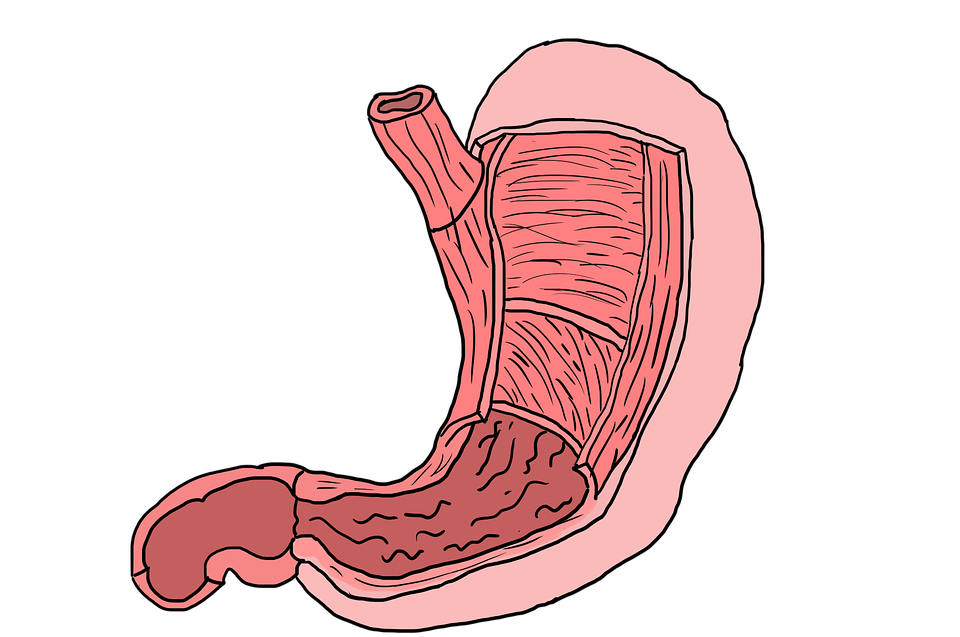

5 – O revestimento do estômago é substituído

Está gostando de conhecer fatos curiosos sobre o seu corpo? Este é mais um bem surpreendente.

O estômago precisa substituir todo o seu revestimento interno a cada dois dias para evitar que o órgão seja completamente destruído pela presença de seu próprio ácido.

Este é um órgão essencial para uma digestão correta. O ambiente ácido do estômago favorece o funcionamento de sua enzimas, essas substâncias são a responsáveis por algumas etapas do processo de quebra do alimento.

Nas paredes do estômago há o muco. Estas células protegem essas regiões deste pH fortemente ácido, porém, ainda assim, a renovação é importante devido ao grande dano que o constante contato com os ácidos podem causar ao órgão.